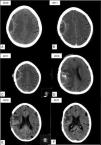

ResultadosSe trata de dos pacientes que posterior a procedimientos quirúrgicos (craniectomía descompresiva por TCE grave y craneotomía por meningioma parietal derecho) desarrollaron colecciones extraaxiales que se mantuvieron vigiladas en el tiempo y que luego se infectaron y precisaron evacuación urgente de las mismas. En estas coleccionas creció el P. acnes como agente causal y precisó antibioterapia dirigida.

ConclusionesDebemos tomar en cuenta al P. acnes como agente infeccioso de colecciones posquirúrgicas de larga evolución. La presentación atípica y los cambios radiológicos pueden ser de ayuda en el diagnóstico.

ResultsThese are two patients who, following surgical procedures (decompressive craniectomy for severe TBI and craniotomy for right parietal meningioma) and extra-axial collections were kept, which were monitored over time and then were infected and required emergency evacuation. In these collections P. acnes grew as a causal agent and required targeted antibiotics.

ConclusionsWe must consider P. acnes as an infectious agent of post-surgical collections of long evolution. Atypical presentation and radiological changes may be helpful in diagnosis.